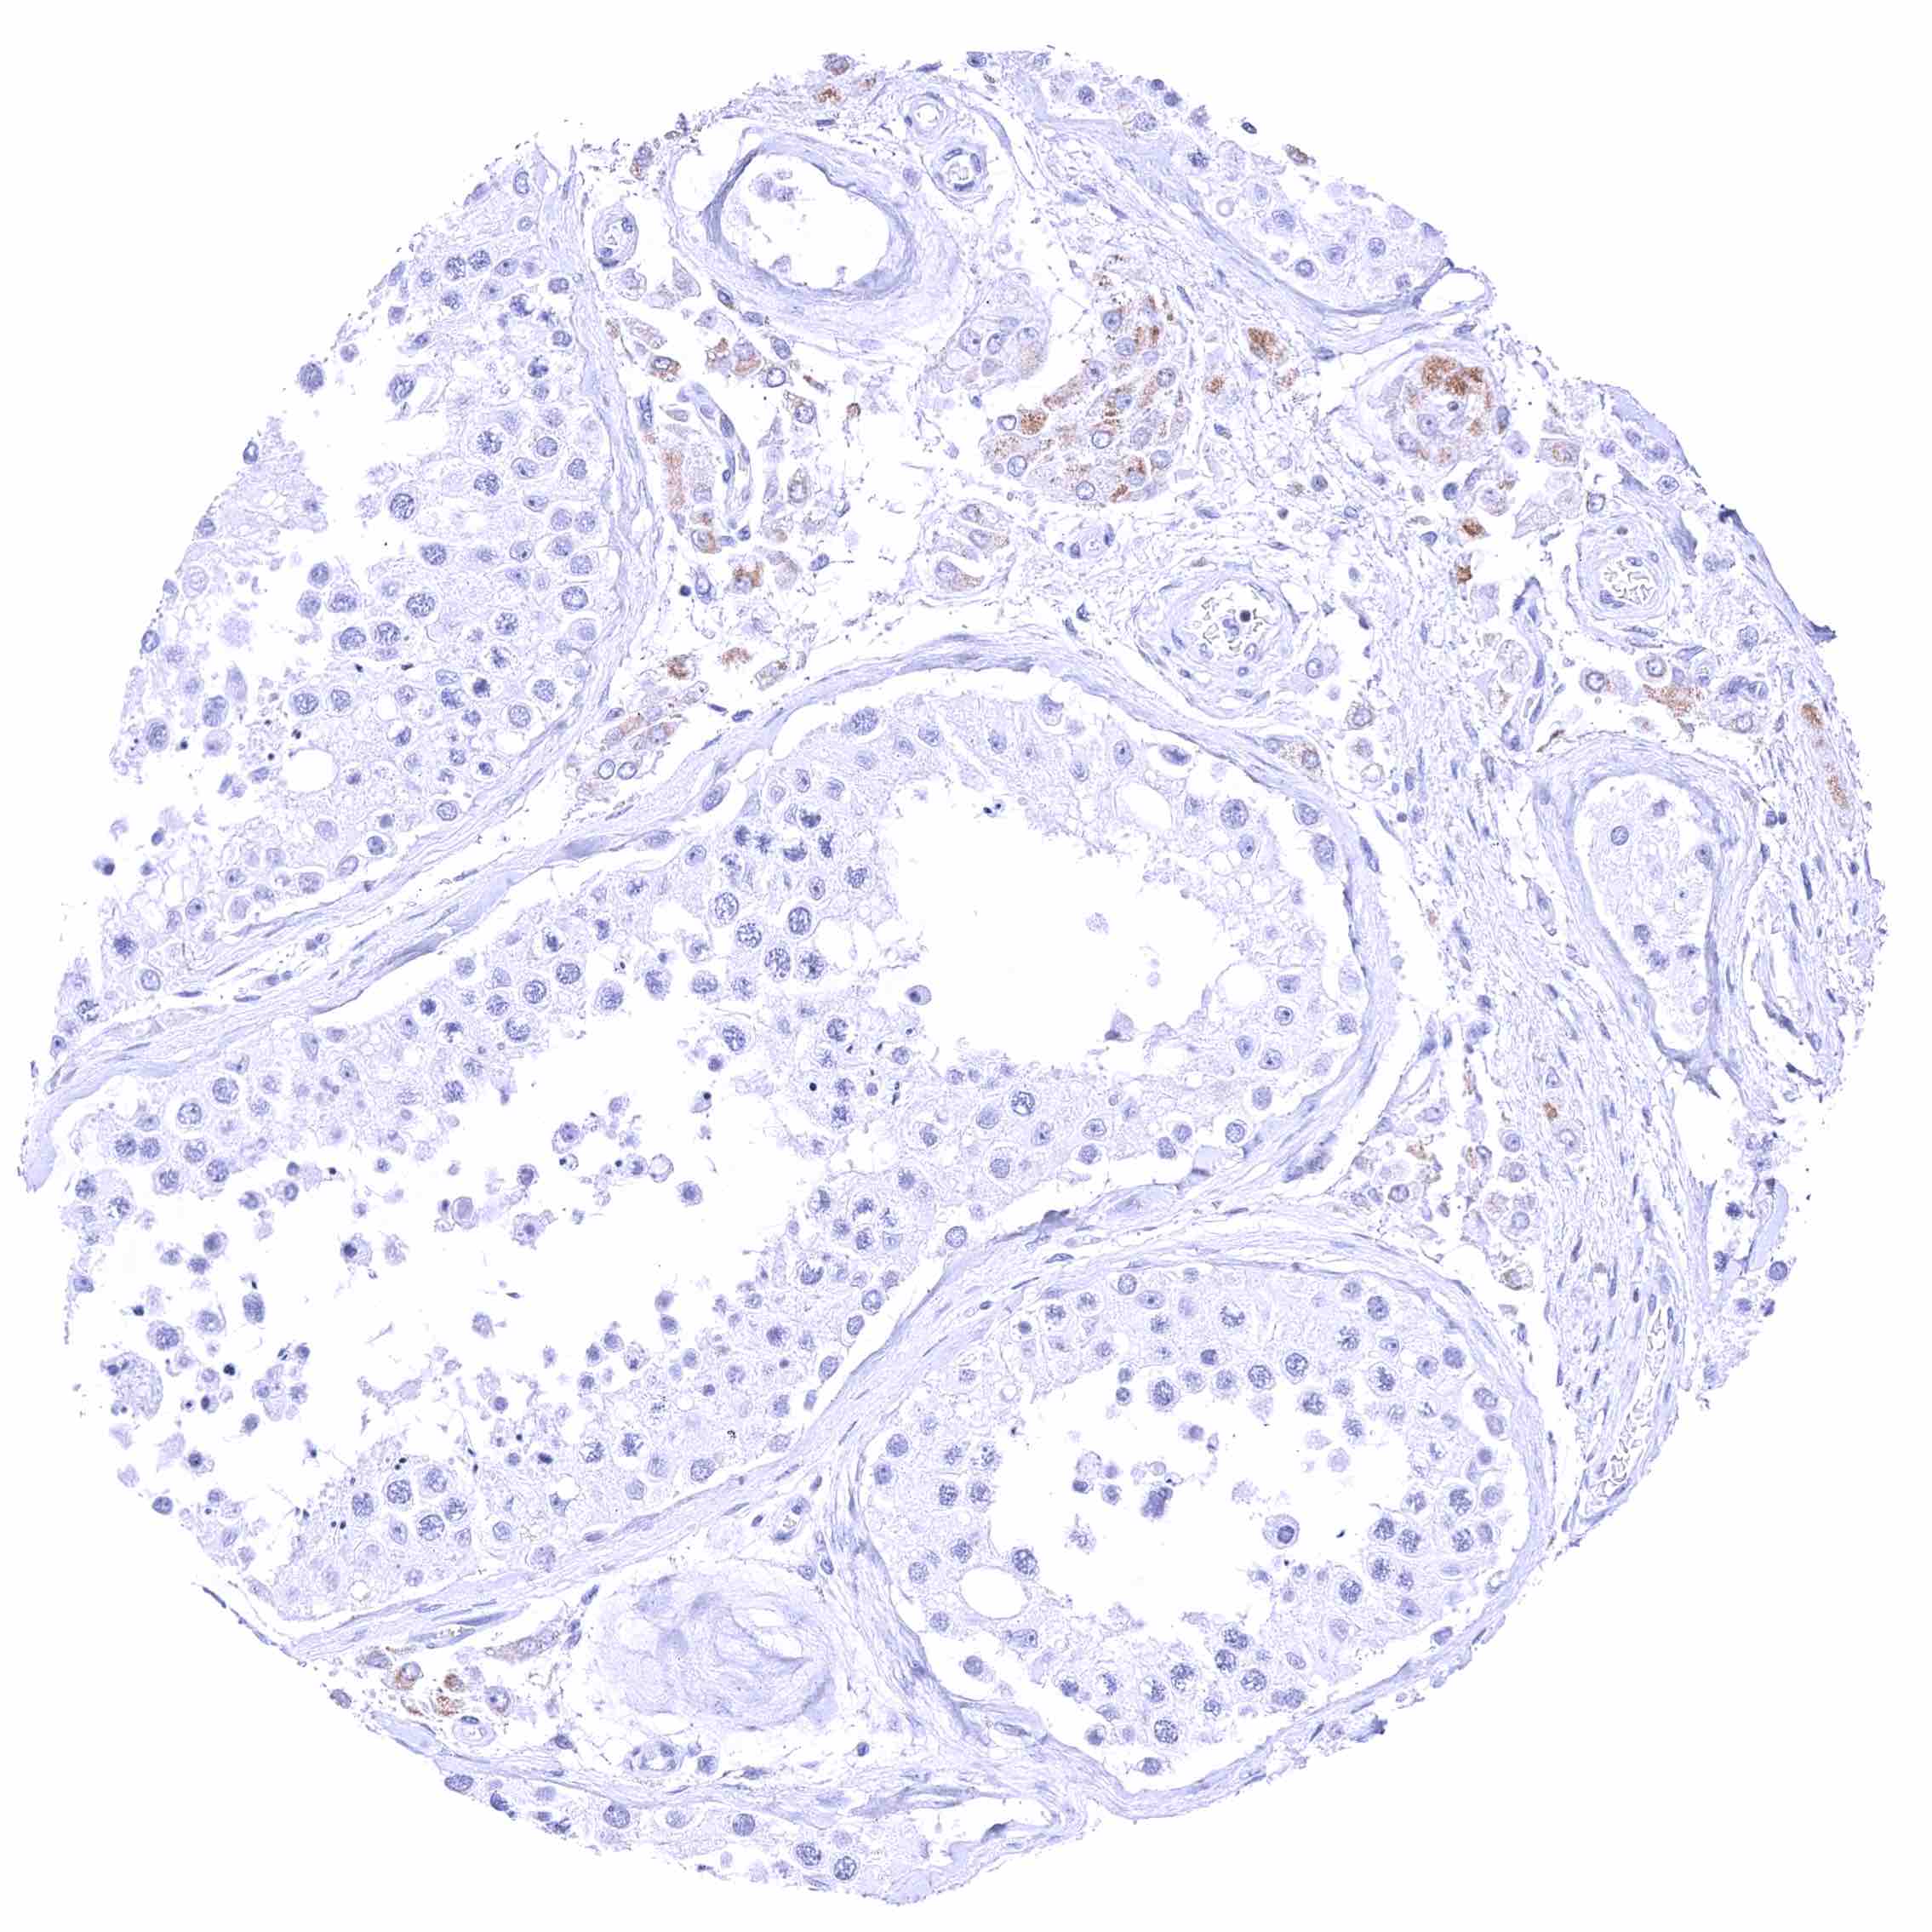

Testis